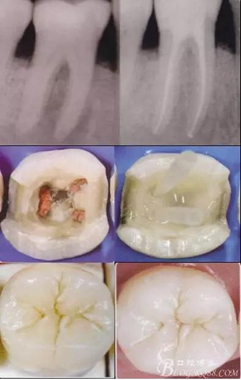

根管治療后高嵌體臨床操作流程:

高嵌體病例圖片